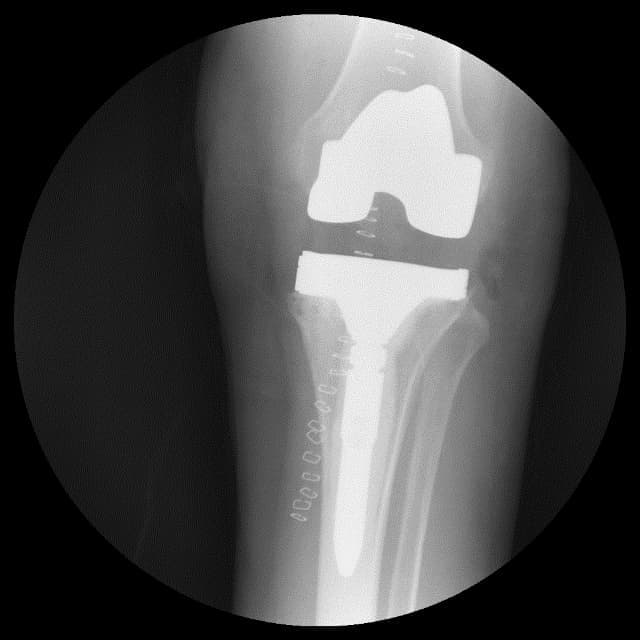

Үе дайрсан ясны анхдагч хавдар, ясны дутмагшлын үед хийгдэх мэс засалimg27Үе дайрсан ясны анхдагч хавдар, ясны дутмагшлын үед хийгдэх мэс засалimg28

Зураг 1. Сэргээн засах мэс заслын өмнөх рентген зураг. Эгц урд, хажуугаас авсан байдал. Халдварын бус шалтгаант хиймэл үений ховхрол.

Үе дайрсан ясны анхдагч хавдар, ясны дутмагшлын үед хийгдэх мэс засалimg29Үе дайрсан ясны анхдагч хавдар, ясны дутмагшлын үед хийгдэх мэс засалimg30

Зураг 2. Мэс заслын дараах рентген зураг. Эгц урд, хажуугаас авсан байдал.

Энэ тохиолдолд зөвхөн шилбэ хэсгийн хиймэл үений ховхрол үүсч, ясны дутмагшилд орсон байв. Шилбэ хэсгийн хиймэл үеийг шинээр солихдоо ясны дутмагшлыг метал блокоор нөхөж, чөмөгт хөндий рүү илүү гүн суулгах extension stem ашигласан.